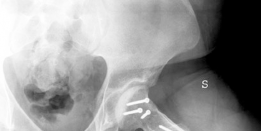

Radiographic evaluation must demonstrate a clear structural conflict, such as an extruded lateral head segment causing hinge abduction, but without advanced joint space narrowing. The presence of a "hinge" can often be confirmed dynamically under fluoroscopy or via abduction-internal rotation plain radiographs.

Standard radiographic series should include an anteroposterior pelvis, cross-table lateral, and false profile views of the affected hip. Functional views, such as maximum abduction and adduction radiographs, help quantify the degree of hinge abduction and the potential for concentric reduction.